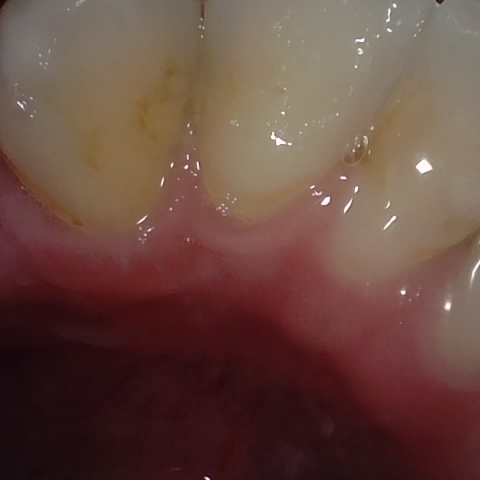

Annotated as "Bad"